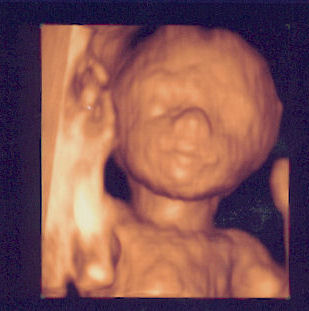

Klar zeig ich euch mal Pünktchen auf den Bild bin doch ganz stolz drauf.

unser Pünktchen

Ach ist das ein süßes Pünktchen :juhu: !!!!!

Ist ja echt toll, was heute so alles möglich ist :o -

bei meiner ersten Schwangerschaft - vor ca. 100 Jahren *g* - gab´s solche tollen Bildchen noch nicht!

Also winni, das Pünktchen habt ihr echt fein "gebastelt" :prima: :prima: :prima: !

Winni, süßes Pünktchen. Frau Dr. Kähler kenn ich gar nicht, aber ich muss hier ja auch nicht alle kennen.

Na das ist ja ein schickes Kerlchen. Gut gemacht. :prima: